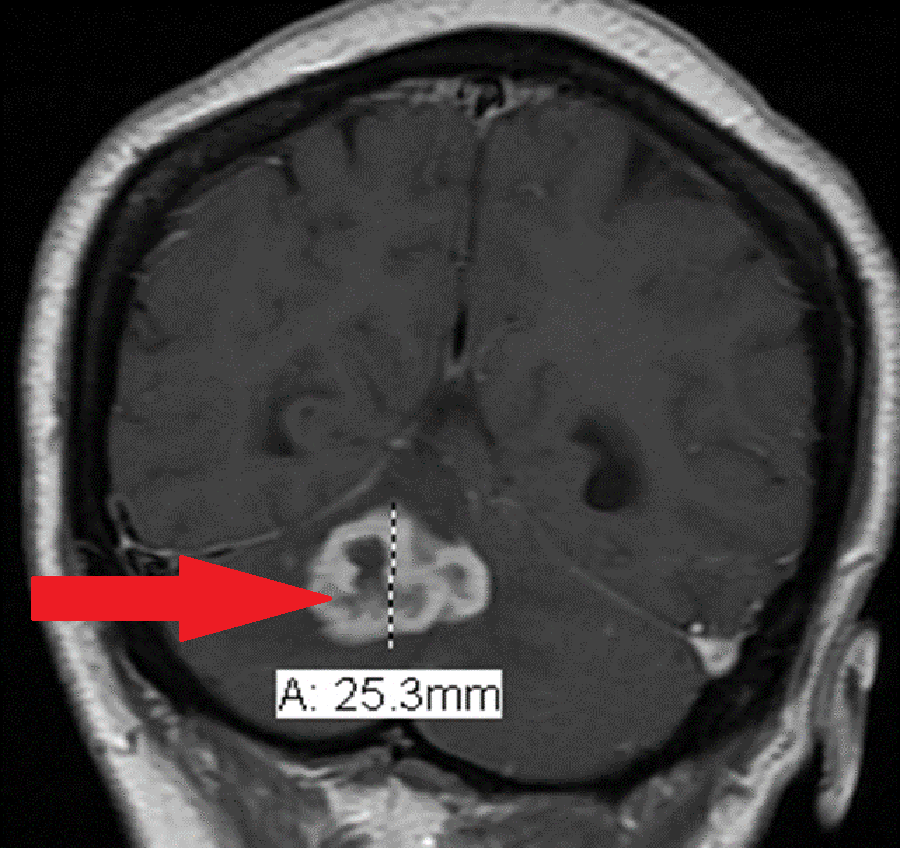

A 48-year-old African American female presented with a one-month history of headaches and nausea. Her only significant past medical history was diabetes. Her social history was negative for such risk factors as a high-risk profession in the healthcare field, recent incarceration, known contact with persons diagnosed with active tuberculosis or recent travel to areas in which tuberculosis is endemic. Her physical exam was unremarkable, and she had no focal neurological deficits. She was afebrile and hemodynamically stable. She presented to an outside facility where she had a computerized tomography (CT) scan of her head performed, which showed a posterior fossa mass with moderate hydrocephalus. This was followed by a magnetic resonance imaging (MRI) of the brain with and without contrast, which revealed a large right cerebellar ring-enhancing mass (Figures 1-2). The primary concern at that time was that this mass could possibly be a primary brain glioma like a high-grade astrocytoma or a medulloblastoma. The patient was transferred to another hospital for neurosurgical evaluation and excision of the mass. She underwent an exploratory posterior fossa craniectomy, cerebellar exploration and decompression, but no mass was identified at that time. Due to persistent headaches, she then had a repeat exploration of posterior fossa 15 days later, and identification and excision of the cerebellar mass occurred. Histopathology from the procedure revealed necrotizing granulomas (Figure 3), and stains specific for acid fast bacilli and fungus were both negative. Subsequently, the brain tissue grew Mycobacterium tuberculosis. The patient reported no prior knowledge of having tuberculosis, nor did she endorse exposure to patients with active tuberculosis. She previously had purified protein derivative (PPD) tests for employment, which had been negative. She was not immunocompromised and had recently been tested negative for human immunodeficiency virus (HIV) six months prior.

Diagnostic imaging with a CT and MRI of the brain show ring-enhancing lesions with intense surrounding edema. Although multiple lesions may be present in up to one-third of patients with a tuberculoma, the patient presented in this case had a solitary brain lesion [9].